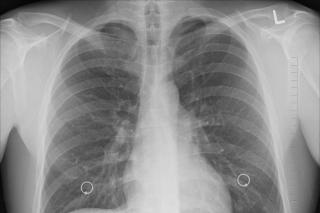

Фото: pixabay.com

Фото: pixabay.com | В топ-5 стран – лидеров по количеству случаев заражения COVID-19 ожидаются изменения